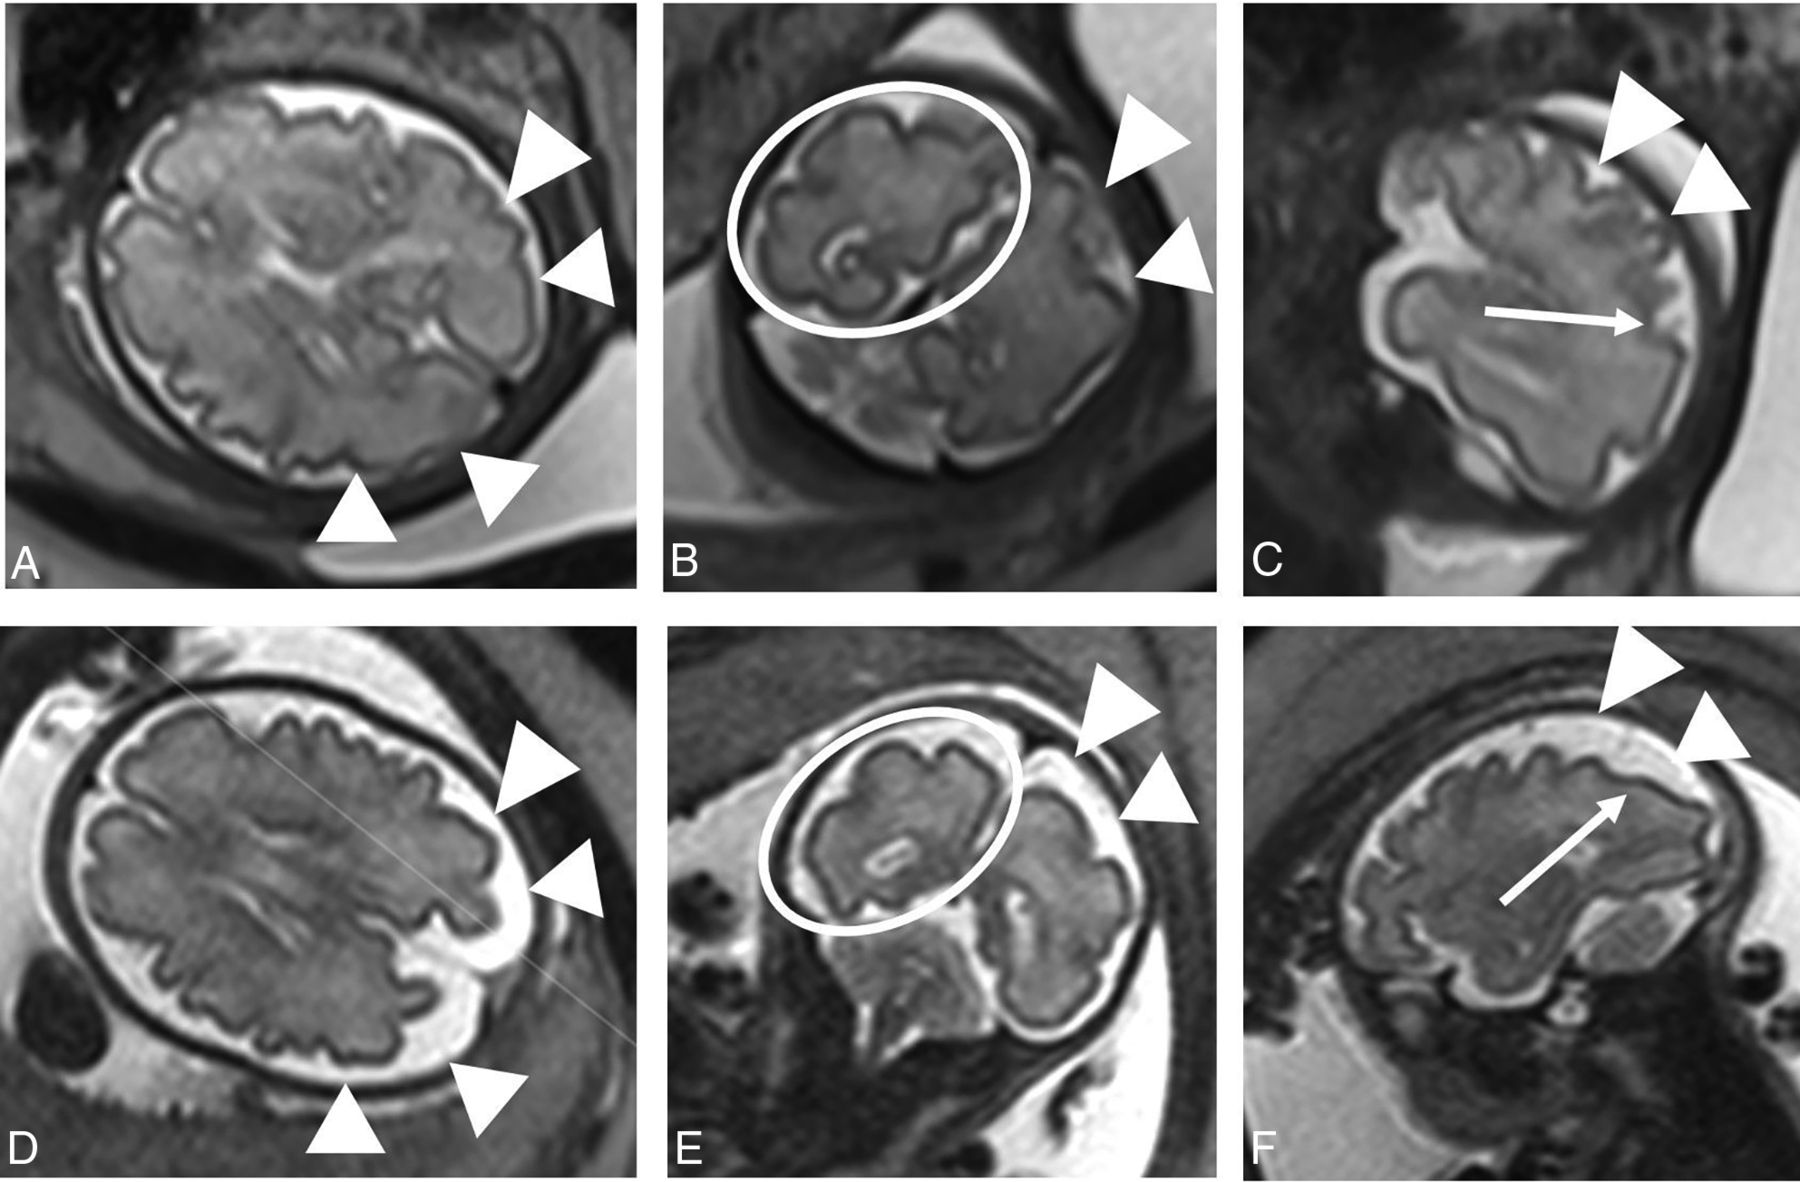

3D super-resolution reconstruction (SRR) volumes were created from the standard T2-weighted 2D stacks displaying the fetal brain, using NiftyMIC (https://github.com/gift-surg/NiftyMIC), a publicly available and state-of-the-art SRR algorithm.23 The SRR volumes were automatically segmented for white matter, the ventricular system (lateral ventricles, third ventricle, fourth ventricle, and aqueduct), the cavum septi pellucidi and cavum vergae, extra-axial space, and cerebellum with manual correction when necessary (D.E. supervised by M.A.). A deep learning algorithm for the automatic segmentation of white matter, the ventricular system, and cerebellum was used for the first volumes that were processed.24 As the number of volumes segmented for the extra-axial space increased, we trained a new deep learning–based segmentation algorithm25 based on a partially supervised learning method that automatically segments white matter, the ventricular system, the cerebellum, and the extra-axial space. These segmentations were used for volumetric analysis when the quality of the SRR volume allowed further analysis (determined by D.E. and supervised by M.A. and L.F.) (Fig 1).

T2-weighted images in the axial (A), coronal (B), and sagittal (C) planes illustrating automated segmentations of the extra-axial space (yellow), white matter (red), ventricular system (green), and cerebellum (blue).